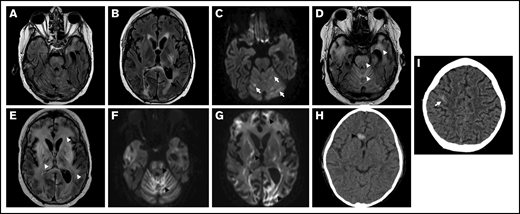

Representative brain imaging findings from patients with TA-TMA are shown in Figure 2. Patient 1 had a brain vascular injury score of 3 and had prominent abnormalities on brain imaging that were attributable to a vascular process (Figure 2A-G). Magnetic resonance images obtained in the setting of neurologic decline demonstrated new areas of abnormal white matter signal in the periventricular and subcortical white matter. Over a course of 3 months, progressive imaging findings included new cortical signal abnormality with diffusion restriction in the occipital lobes, initially raising concerns for PRES, as well as progressive multifocal brainstem, cerebellar, basal ganglia, and white matter signal abnormalities. Progressive diffusion restriction in the occipital lobes and new, small, intraparenchymal hemorrhages occurred. Patient 3 experienced AMS after autologous HCT for neuroblastoma. Head computed tomography was performed and showed multiple areas of acute hemorrhage (Figure 2H–I). The patient was diagnosed with TA-TMA on the same day, according to laboratory criteria.

CNS radiographic abnormalities in TA-TMA. An 18-year-old man (patient 1 in Table 1) experienced progressive neurologic decline after HCT and underwent magnetic resonance imaging (A-G) on day 124 after HCT. He was diagnosed with TA-TMA on day 39. (A-B) Axial fluid-attenuated inversion recovery (FLAIR) images demonstrate multifocal areas of signal abnormality (black arrows) in the cerebellum, brainstem, periventricular white matter, and posterior limb of the left internal capsule and adjacent basal ganglia. (C) A T2-trace diffusion–weighted image demonstrates corresponding diffusion restriction predominantly within areas of signal in the cerebellum (white arrows). (D-E) Progressive hyperintense signal abnormality on FLAIR throughout the cerebellum, brainstem, cerebral white matter, and deep gray nuclei (white arrowheads). (F-G) Diffusion-weighted imaging demonstrates corresponding progressive diffusion restriction (black arrowheads). A 4-year-old patient with neuroblastoma (patient 3 in Table 1) experienced altered mental status on day 10 after autologous HCT and underwent a head CT (H-I). TA-TMA was diagnosed on the same day. Axial computed tomographic images demonstrate a new, ovoid, high-attenuation hemorrhage in the genu of the corpus callosum (arrowhead), as well as a more subtle hemorrhage along the cortical surface of the posterior right frontal lobe (arrow).

Six patients demonstrated parenchymal hemorrhages in the cortex, deep gray matter, and/or corpus callosum. Regional areas of diffusion restriction were present in 5 patients. One patient had superficial siderosis and multifocal punctate parenchymal hemorrhages. Four patients presented with imaging findings concerning for PRES within weeks of their TMA diagnosis.